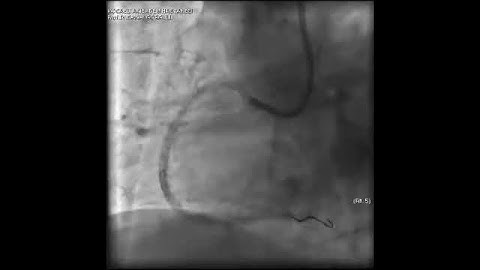

Complex PCI for RCA CTO with bifurcation at distal cap video 16